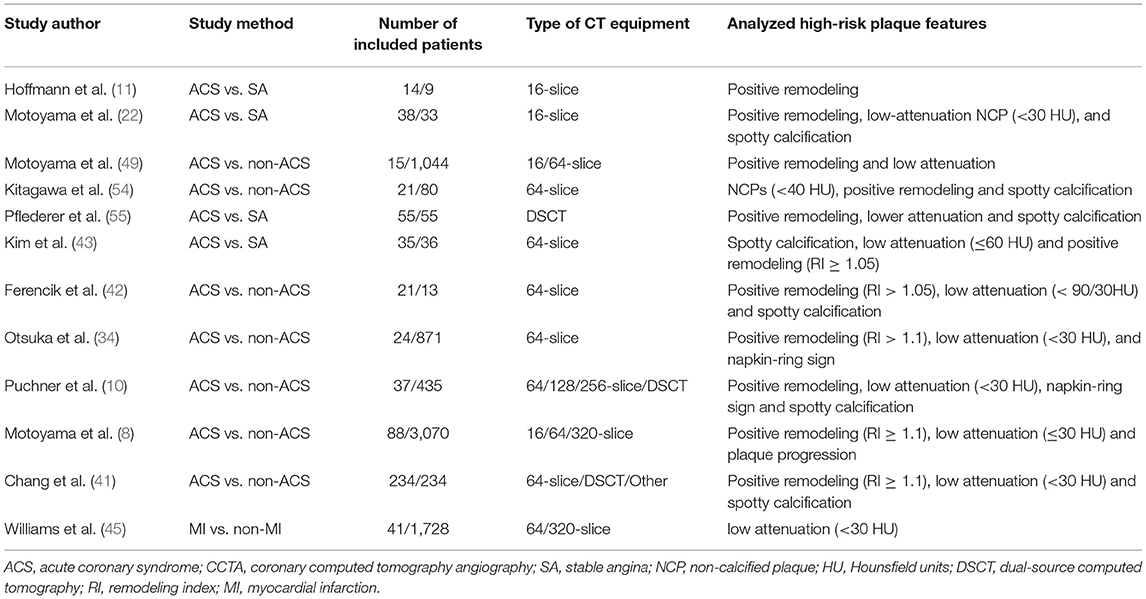

Although the risk of plaque instability increases with the degree of coronary stenosis, most of the culprit lesions found in ACS are considered non-obstructive before rupture. Previous studies indicated that the characteristics of high-risk plaques identified by CCTA have a prognostic value independent of stenosis and atherosclerotic burden (41) (see Table 1).

The characteristics of high-risk plaques are related to the vulnerability of plaques (18). Based on the histopathologic composition of vulnerable plaques, including thin cap fibroatheroma, macrophage infiltration, and necrotic core (20, 21), the corresponding typical manifestations of high-risk plaques in CCTA are listed as follows: positive remodeling, low attenuation, spotty calcification, and napkin-ring sign (22–24) (Figure 1).

Figure 1. From high-risk plaque histopathology to CCTA. The figure shows the histopathologic components of vulnerable plaques (colored illustrations) and the corresponding typical CT features of high-risk plaques: (A) positive remodeling, (B) low attenuation, (C) spotty calcification, and (D) napkin-ring sign. CCTA, coronary computed tomography angiography.